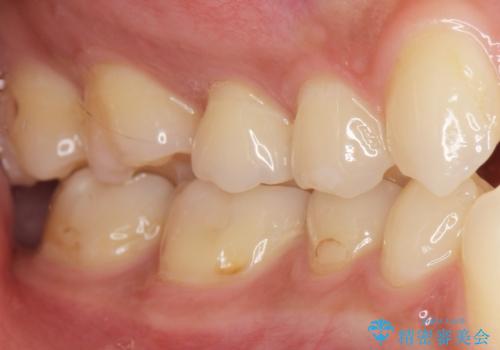

- 奥歯にフロスを通すとにおいがすることを気にされ、来院された患者様です。

精査したところ、奥歯に充填された保険内のコンポジットレジンの適合が悪いことにより、汚れがたまりやすい状態でした。

不適合なレジンを除去し、セラミックインレーによる治療を行いました。(右上76左上67右下7の計5本)

気にされていたフロスをした時のにおいがなくなり、喜んで頂けました。

治療終了後半年のメンテナンス時には「咬み合わせもばっちりです!」とおっしゃって下さいました。